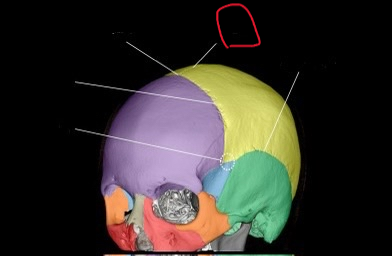

anth 1400 lab exam 1 cranial, skull shit

sphenoid bone (lateral)

also greater wing

frontal bone (lateral)

ethmoid bone (lateral)

also orbital plate

temporal bone (lateral)

occipital bone (lateral)

parietal bone (lateral)

coronal suture (lateral)

pterion

coronal suture (suture)

bregma

sagittal suture

squamosal suture

lambdoid suture